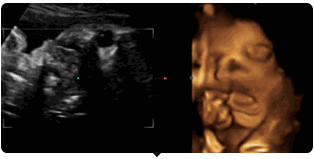

好困,打哈欠

揉眼睛

麻麻,我在挠耳朵

嚯嚯~打拳啦!

甘谷四维彩超,骨密度检测,清晰度高,显示准确,受到了患者的一致好评。

四维彩色超声诊断仪出色的人体工程学设计,不存在射线、光波和电磁波等方面的辐射,对人体的健康没有任何影响。